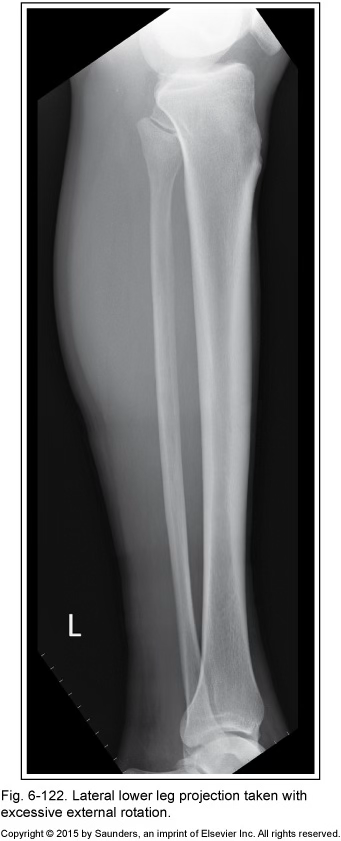

lateral tib fib

excessive external rotation